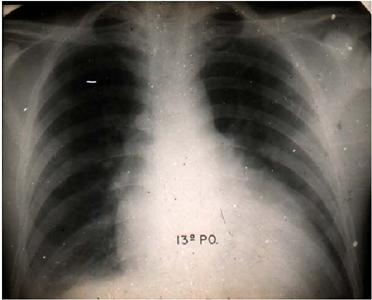

The first recipient was a patient with dilated cardiomyopathy, and the donor was a patient with skull trauma, loss of brain tissue through the wound, and tracheotomy. Electroencephalogram was performed, with physical and light stimulation to confirm brain death diagnosis made by an independent neurologist. A canula was inserted in the innominate artery and connected to a cardiopulmonary bypass circuit. Ventilation was discontinued and it was waited until heartbeat stopped. Then a selective perfusion of the heart was started, and the donor heart was harvested. Meanwhile, the recipient was prepared, in an adjacent operating room, and the heart was resected. The perfused donor heart was transported in a basin and prepared in the recipient operating room. Cardiac transplantation was done by the so-called conventional technique. The recipient by the name of João Ferreira became in the media nationwide known as João “boiadeiro” (Figures 4 and 5). He survived 28 days and died from refractory acute rejection (Figure 5). Two other patients were transplanted by Dr. Zerbini in 1968 and 1969; one (the second) survived more than one year (Figure 6), and the other (the third) survived for 60 days.